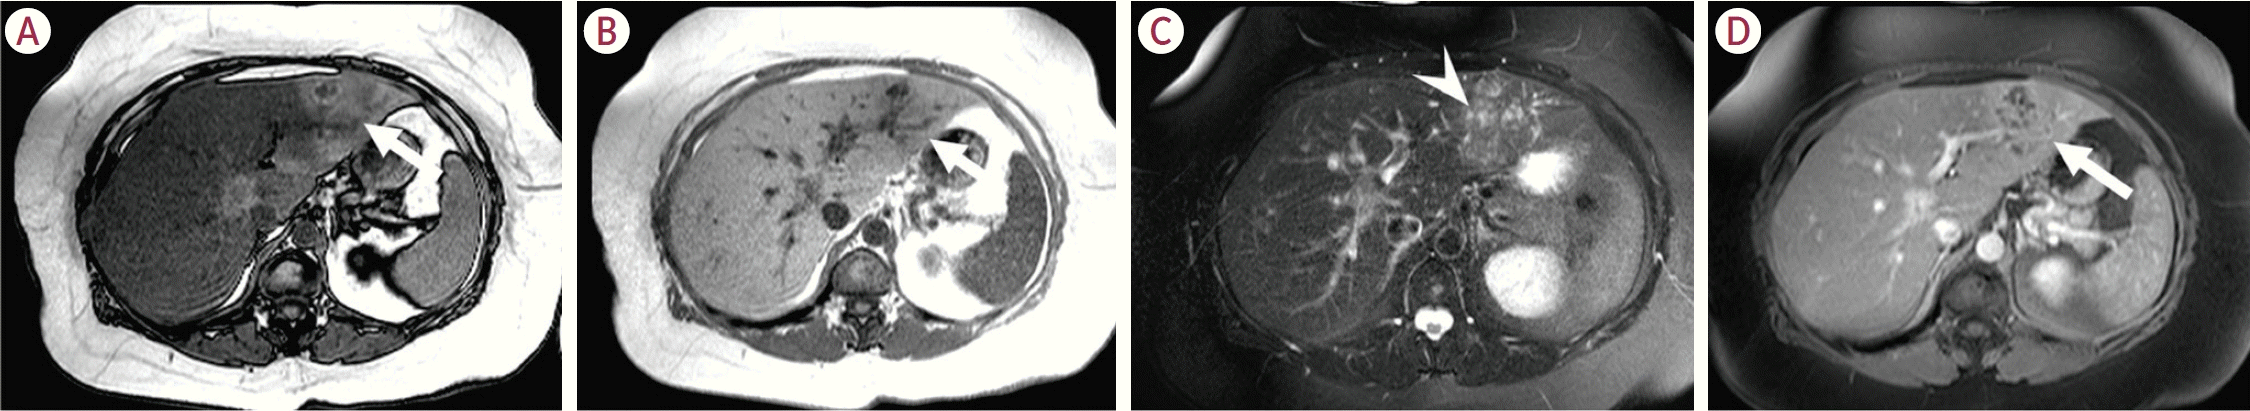

30. Laumonier H, Bioulac-Sage P, Laurent C, Zucman-Rossi J, Balabaud C, Trillaud H. Hepatocellular adenomas: magnetic resonance imaging features as a function of molecular pathological classification. Hepatology. 2008; 48:808–818.

31. van Aalten SM, Thomeer MG, Terkivatan T, Dwarkasing RS, Verheij J, de Man RA, et al. Hepatocellular adenomas: correlation of MR imaging findings with pathologic subtype classification. Radiology. 2011; 261:172–181.

32. Ba-Ssalamah A, Antunes C, Feier D, Bastati N, Hodge JC, Stift J, et al. Morphologic and molecular features of hepatocellular adenoma with gadoxetic acid-enhanced MR imaging. Radiology. 2015; 277:104–113.

33. Bise S, Frulio N, Hocquelet A, Alberti N, Blanc JF, Laurent C, et al. New MRI features improve subtype classification of hepatocellular adenoma. Eur Radiol. 2019; 29:2436–2447.

40. Glockner JF, Lee CU, Mounajjed T. Inflammatory hepatic adenomas: characterization with hepatobiliary MRI contrast agents. Magn Reson Imaging. 2018; 47:103–110.

41. Agarwal S, Fuentes-Orrego JM, Arnason T, Misdraji J, Jhaveri KS, Harisinghani M, et al. Inflammatory hepatocellular adenomas can mimic focal nodular hyperplasia on gadoxetic acid-enhanced MRI. AJR Am J Roentgenol. 2014; 203:W408–W414.